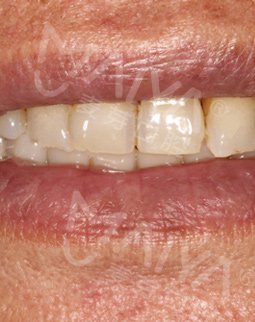

我种牙后并没有什么不适,下牙的牙齿种好了,我又找麦芽的硕博专家把上牙的几颗牙齿也种了,绝对不能因为一颗坏牙再引发其他的口腔问题。临时牙冠佩戴没有任何不适,做了永久修复,而且麦芽的硕博专家还给我分析下牙和上牙的咬合关系,不能随便就戴牙冠,种的好是一方面,更重要的是咬合和使用功能。

这两年陆续去麦芽复诊,医生看完我的牙齿说维护的很好,需要坚持下去,不能因为种完牙就对它不管不顾,按时刷牙和用牙线清洁,据说我的种植牙维护的好可以用上好几十年,每天成本顶多才6毛钱,跟之前的假牙相比又美观,又舒服。

当然我还顺带参加了一下他们的活动,比如分享会、疑难缺牙工程等,跟同样缺牙的老伙计们讲了一下我的故事,分享了一下种牙经历,不得不说自从种完牙后生活发生了巨大的变化,不仅现在可以吃小龙虾、大闸蟹、排骨这些硬菜,还有一些“硬”水果现在也可以吃了,不再以稀饭和面条为主,生活又开始变得有滋有味,现在我的朋友都说我开朗了不少,之前合影都是抿着嘴,现在拍照都是哈哈大笑。